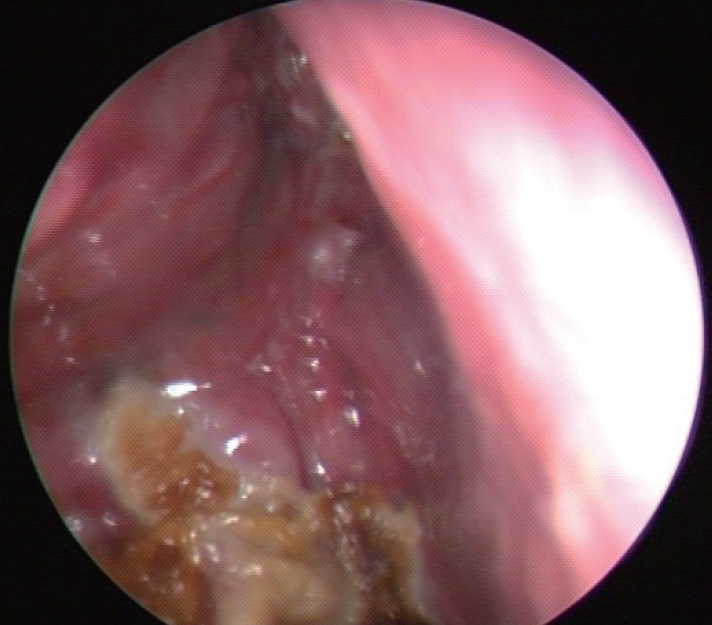

CaseA 59-year-old male presented to the emergency department with profound lethargy, progressive headache, personality changes and mood swings. The symptoms had developed since the last 1 week. The patient had a history of diabetes and depressive disorder, which was diagnosed recently based on the above mentioned symptoms; and he had undergone ESS 6 weeks ago. He had visited our outpatient clinic with a 2-month history of nasal obstruction and epistaxis. He had already been diagnosed as having chronic rhinosinusitis and nasal polyps, but there was no response to medical treatment. In the contrast computed tomography (CT) scan of his paranasal sinuses, there was a soft tissue mass that had completely filled the right maxillary sinus and was extending into the nasal cavity with widening of the maxillary ostium, the ethmoidal infundibulum, and lifting of the ethmomaxillary plate. This mass was diagnosed as inverted papilloma (Fig. 1). He underwent right endoscopic medial maxillectomy under general anesthesia and the diagnosis of inverted papilloma was confirmed by frozen biopsy. Intraoperatively, it was noted that the mass was penetrating into the anterior skull base and there was a 1.5-cm dural defect resulting in CSF leakage following the surgery. The defect was repaired using an underlay technique with the inferior turbinate mucosal flap, and the septal cartilage was sealed with a fibrin sealant Tissucol Duo Quick® (Baxter AG, Vienna, Austria). The lumbar drain was maintained for 3 days postoperatively. He was discharged from the hospital on the seventh day after surgery. During the follow-up period, 3 days before the visiting the emergency room, he complained of non-locaized mild headache and mild lethargy. Also, no obvious CSF leakage was detected on nasal endoscopy (Fig. 2).

NotesAuthor Contribution Conceptualization: Jin Kook Kim. Data curation: Hansol Kim, Taesik Jung. Formal analysis: Hansol Kim, Taesik Jung, Jin Kook Kim. Methodology: Jin Kook Kim. Project administration: Joon Yong Park, Jin Kook Kim. Supervision: Jin Kook Kim. Visualization: Hansol Kim, Taesik Jung. Writing—original draft: Joon Yong Park. Writing—review & editing: Jin Kook Kim. Fig. 1.In the CT scan of paranasal sinuses, the right maxillary sinus was filled with a heterogeneous soft tissue mass. The mass was extending into the nasal cavity with widening of the maxillary ostium. Fig. 2.Endoscopic finding of the dural repair site. There was no cerebrospinal fluid leakage at postoperative 6 weeks. REFERENCES1. DelGaudio JM, Ingley AP. Treatment of pneumocephalus after endoscopic sinus and microscopic skull base surgery. Am J Otolaryngol 2010;31(4):226-30.